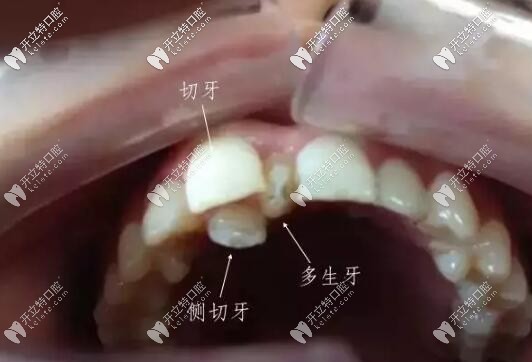

萌出的多生牙

智齒和多生牙并不是一個(gè)概念。多生牙從形態(tài)、牙根的數(shù)量,均不同于正常牙。